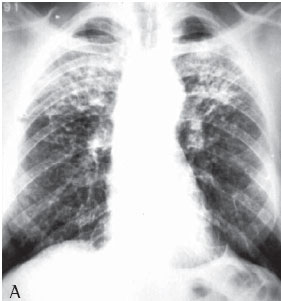

RESULTS

All 75 patients with accelerated silicosis were male. The mean age was 43 years (range, 28-76 years). The mean duration of exposure was 14.2 years (range, 7 months-38 years). Of the 75 patients, 62 (82.6%) were sandblasters, 11 (14.6%) were blacksmiths, 1 (1.4%) was a welder, and 1 (1.4%) was a metal polisher. In reference to concomitant tuberculosis, 39 patients reported a history of pulmonary tuberculosis (52%). Of those, 37 developed the disease during their exposure to silica.The diagnosis was confirmed in 31 cases: 24 through direct sputum smear microscopy; 3 through direct mycobacteria culture of the sputum; 1 through mycobacteria culture of the bronchoalveolar lavage fluid; and 3 through histopathology. In 8 patients, there was clinical and radiological suspicion of tuberculosis based on a response to specific treatment. The radiological classification of the large opacities seen on the chest X-rays was as follows: Type A in 23 patients (30.7%); Type B in 25 (33.3%); and Type C in 27 (36%) (Figures 1A and 1B). Of the cases analyzed, 74 presented bilateral conglomerate masses, whereas only 1 presented unilateral lesion (Figures 2A and 2B).

On a simple chest X-ray, accelerated silicosis is characterized by large opacities (over 1 cm in diameter), with nonsegmentally distributed, homogenous areas of consolidation, principally affecting the upper fields.

The chest X-rays of more than half of the accelerated silicosis patients showed large type B or C opacities, denoting the seriousness of the disease in these patients.